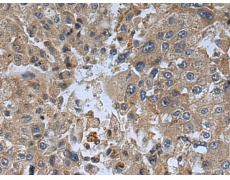

IHC positive control: |

Human liver cancer and Human thyroid cancer |

IHC Recommend dilution: |

150-300 |